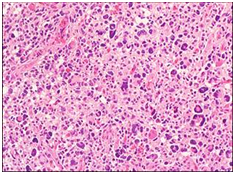

根据肿瘤的组织学特点,星形细胞瘤可分为纤维型、原浆型、肥胖细胞型等类型。下面是在显微镜下的常见的星形细胞瘤分型。

肥胖性星形细胞瘤 间变性星形细胞瘤